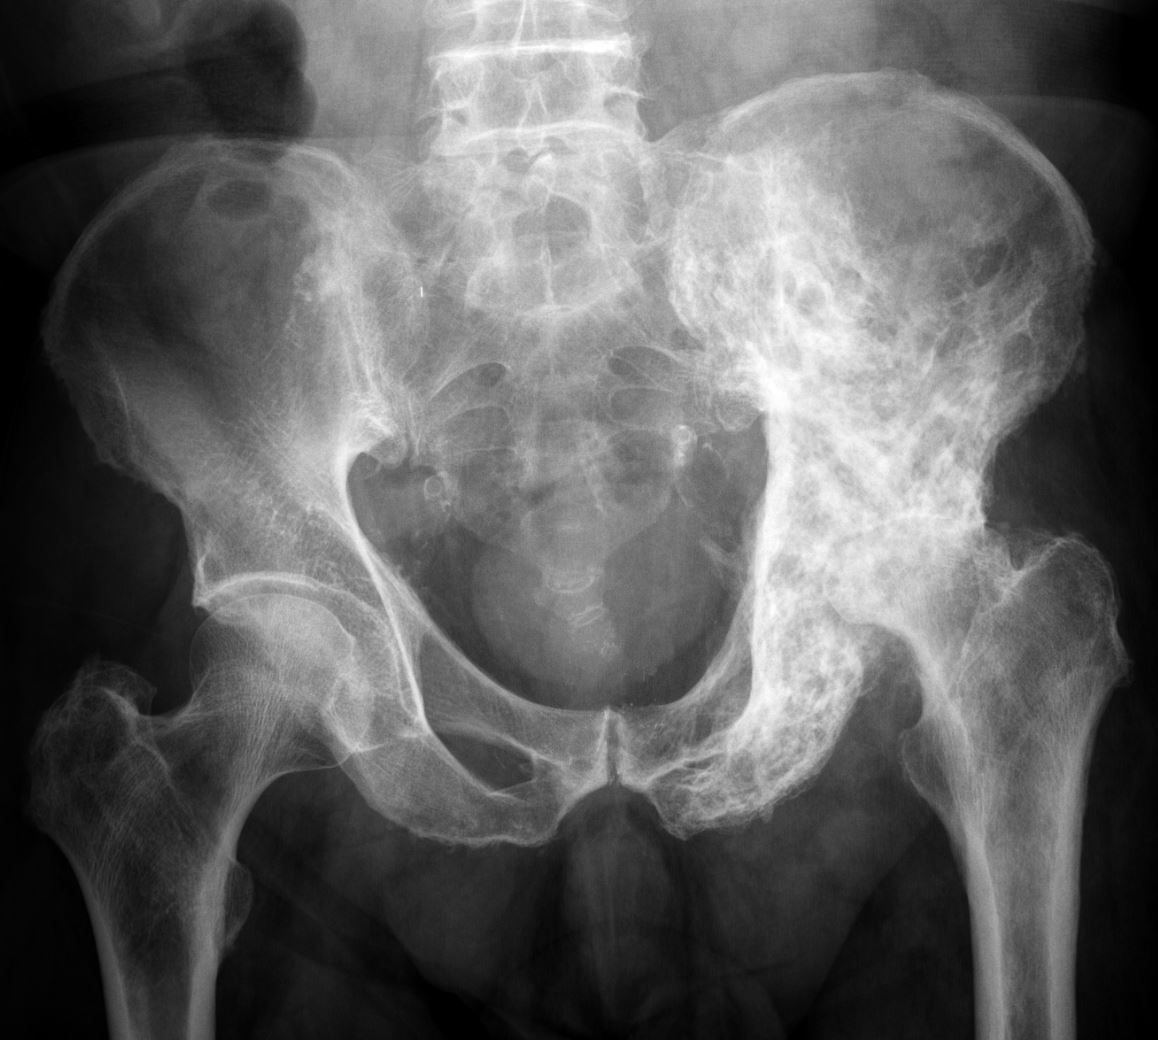

Image XRay of the Pelvis in Paget Disease MSD Manual Professional Paget's Disease Sacrum In many cases, individuals are unaware that they. The anatomic distribution of paget disease usually is asymmetric and most commonly affects the lumbar spine. Many people who have paget’s disease do not have symptoms and never develop complications. A deadly complication of paget disease is the development of pagetic sarcoma, a tumor that can be fatal. Paget's disease of the. Paget's Disease Sacrum.

Learning Radiology paget, disease, paget's, pelvis Paget's Disease Sacrum A deadly complication of paget disease is the development of pagetic sarcoma, a tumor that can be fatal. The cause of paget disease remains unknown, but there are genetic and. The anatomic distribution of paget disease usually is asymmetric and most commonly affects the lumbar spine. The symptoms of paget’s disease vary widely. Paget’s disease (pd) is a chronic metabolically. Paget's Disease Sacrum.